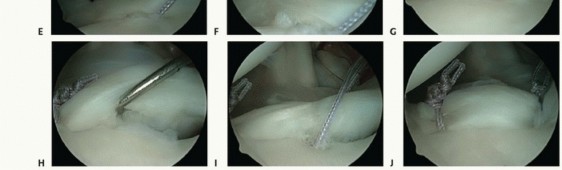

An arthroscopic rasp or chisel is used to mobilize any torn labrum from the glenoid rim (

TECH FIG 1A

).

A motorized synovial shaver or meniscal rasp is used to abrade the capsule adjacent to a labral tear and to débride and decorticate the glenoid rim to achieve a bleeding surface for capsular plication (

TECH FIG 1B

TECH FIG 1 • A. Rasping capsule to stimulate healing after capsular plication. B. Capsular/glenoid abrasion with a motorized shaver.